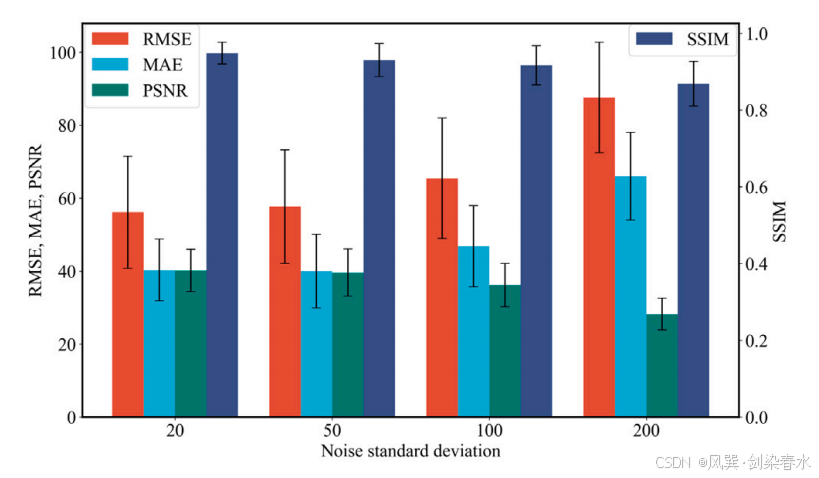

Figure 7 | 不同程度的噪声对模型鲁棒性的影响: